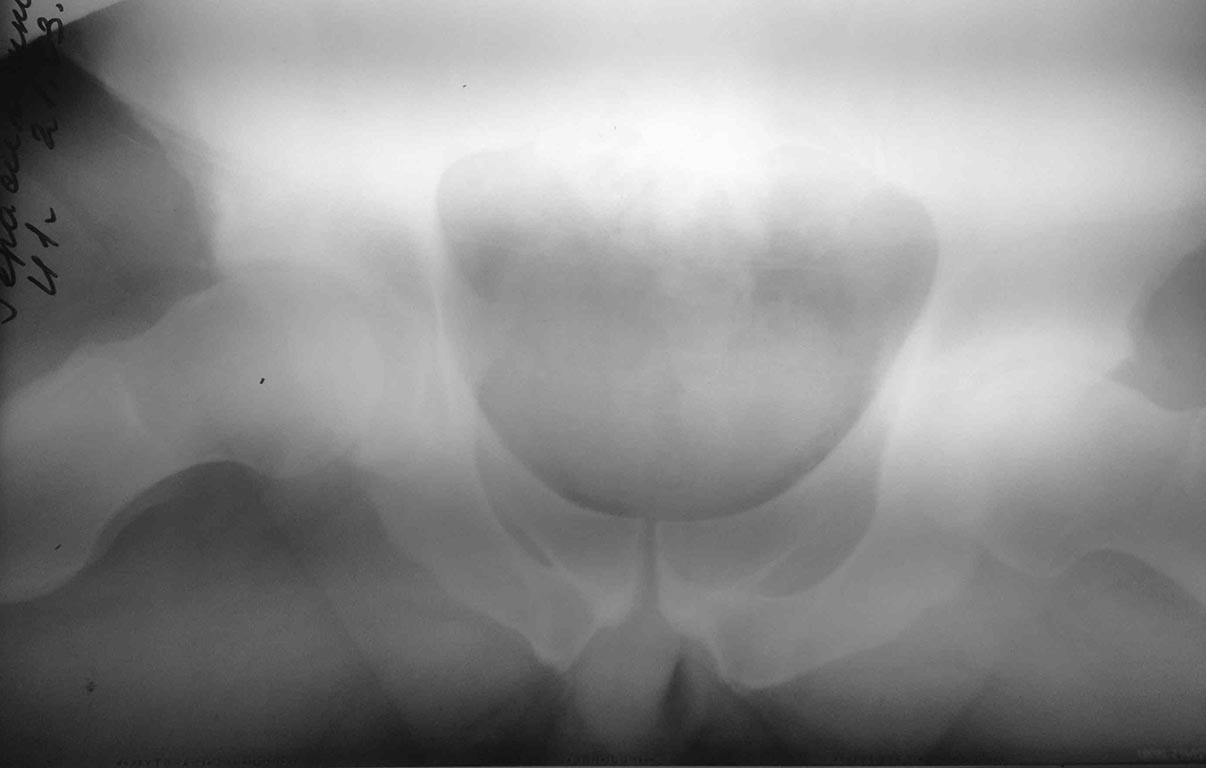

Еще раз извиняюсь за качество снимков, это так, в плане скрининга. В

ближайшее время постараюсь выложить человеческие снимки, включая False

Profile, КТ с 3D, MРТ (c гадолинием не обещаю). Буду выкладывать, по

мере получения информации.